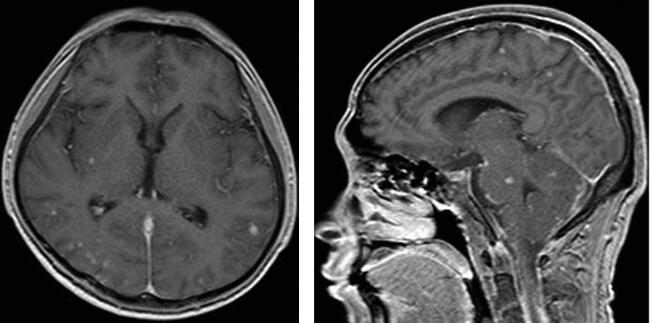

扫描采用PHILIPS ACHIEVA 1.5T超导型磁共振扫描系统,8通道头部线圈,患者取仰卧位,双上肢平置于身体两侧。采用T1加权成像(T1WI)和FLAIR,FFE序列,进行横断位及矢位扫描。采用钆布醇注射液7.5ml,经手背静脉注入,3分钟后扫描。MRI表现见图1。

图1脑内多发结核瘤伴结核性脑膜炎

脑内多发结核瘤伴结核性脑膜炎